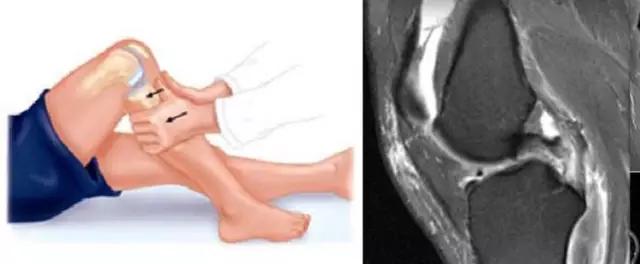

半月板损伤的分度——

Normal:正常的半月板为均匀的低信号。Grade1:半月板内部小灶性的类圆形信号增高影,未达半月 板表面,代表退变性改变。Grade2:半月板内部线形的中等信号增高影,未达半月板表面,代表退变性改变。Grade3:达到半月板关节面的异常信号,可为线形或不规则形,通常代表半月板撕裂。韧带损伤的分级(对所有韧带适用)——Grade1:韧带内损伤,无长度改变。Grade2:韧带内损伤并长度延长。Grade3:完全性韧带撕裂。

熟知诊断标准——

MRI并不能包罗万象,对疾病的诊断率有高有低,根据疾病选择。例如半月板损伤的诊断,MRl的诊断符合率高达95%,而常用的临床检查-麦氏征的诊断符合率仅40%,毫无疑问应该花费更多精力在阅片上,而不是死保某些“体征”。